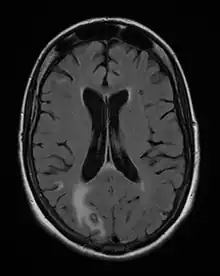

Acute toxoplasmosis is often asymptomatic in healthy adults.[13][14] However, symptoms may manifest and are often influenza-like: swollen lymph nodes, headaches, fever, and fatigue,[15] or muscle aches and pains that last for a month or more. It is rare for a human with a fully functioning immune system to develop severe symptoms following infection. People with weakened immune systems are likely to experience headache, confusion, poor coordination, seizures, lung problems that may resemble tuberculosis or Pneumocystis jirovecii pneumonia (a common opportunistic infection that occurs in people with AIDS), or chorioretinitis caused by severe inflammation of the retina (ocular toxoplasmosis).[15] Young children and immunocompromised people, such as those with HIV/AIDS, those taking certain types of chemotherapy, or those who have recently received an organ transplant, may develop severe toxoplasmosis. This can cause damage to the brain (encephalitis) or the eyes (necrotizing retinochoroiditis).[16] Infants infected via placental transmission may be born with either of these problems, or with nasal malformations, although these complications are rare in newborns. The toxoplasmic trophozoites causing acute toxoplasmosis are referred to as tachyzoites, and are typically found in various tissues and body fluids, but rarely in blood or cerebrospinal fluid.[17]

Due to the absence of obvious symptoms,[13][14] hosts easily become infected with T. gondii and develop toxoplasmosis without knowing it. Although mild, flu-like symptoms occasionally occur during the first few weeks following exposure, infection with T. gondii produces no readily observable symptoms in healthy human adults.[7][20] In most immunocompetent people, the infection enters a latent phase, during which only bradyzoites (in tissue cysts) are present;[21] these tissue cysts and even lesions can occur in the retinas, alveolar lining of the lungs (where an acute infection may mimic a Pneumocystis jirovecii infection), heart, skeletal muscle, and the central nervous system (CNS), including the brain.[22] Cysts form in the CNS (brain tissue) upon infection with T. gondii and persist for the lifetime of the host.[23] Most infants who are infected while in the womb have no symptoms at birth, but may develop symptoms later in life.[24]

In its lifecycle, T. gondii adopts several forms.[32] Tachyzoites are responsible for acute infection; they divide rapidly and spread through the tissues of the body. Tachyzoites are also known as "tachyzoic merozoites", a descriptive term that conveys more precisely the parasitological nature of this stage.[33] After proliferating, tachyzoites convert into bradyzoites, which are inside latent intracellular tissue cysts that form mainly in the muscles and brain. The formation of cysts is in part triggered by the pressure of the host immune system.[34] The bradyzoites (also called "bradyzoic merozoites") are not responsive to antibiotics. Bradyzoites, once formed, can remain in the tissues for the lifespan of the host. In a healthy host, if some bradyzoites convert back into active tachyzoites, the immune system will quickly destroy them. However, in immunocompromised individuals, or in fetuses, which lack a developed immune system, the tachyzoites can run rampant and cause significant neurological damage.[32]

The classic triad of congenital toxoplasmosis includes: chorioretinitis, hydrocephalus, and intracranial arteriosclerosis.[75] Other consequences include sensorineural deafness, seizures, and intellectual disability.[76]